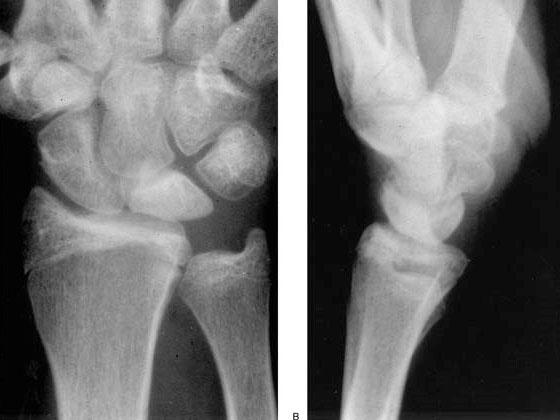

Alteraciones mecánicas o anatómicas, como una discrepancia en la longitud de los huesos: tener un cúbito corto (figuras 1 y 2) y una determinada forma anatómica de semilunar (tipo I) (figura 3).

Figuras 1 y 2: cúbito minus o corto (predisponente de Kienböck)

Figura 3: tipos de formas del semilunar. Mayor riesgo el tipo I con cúbito corto